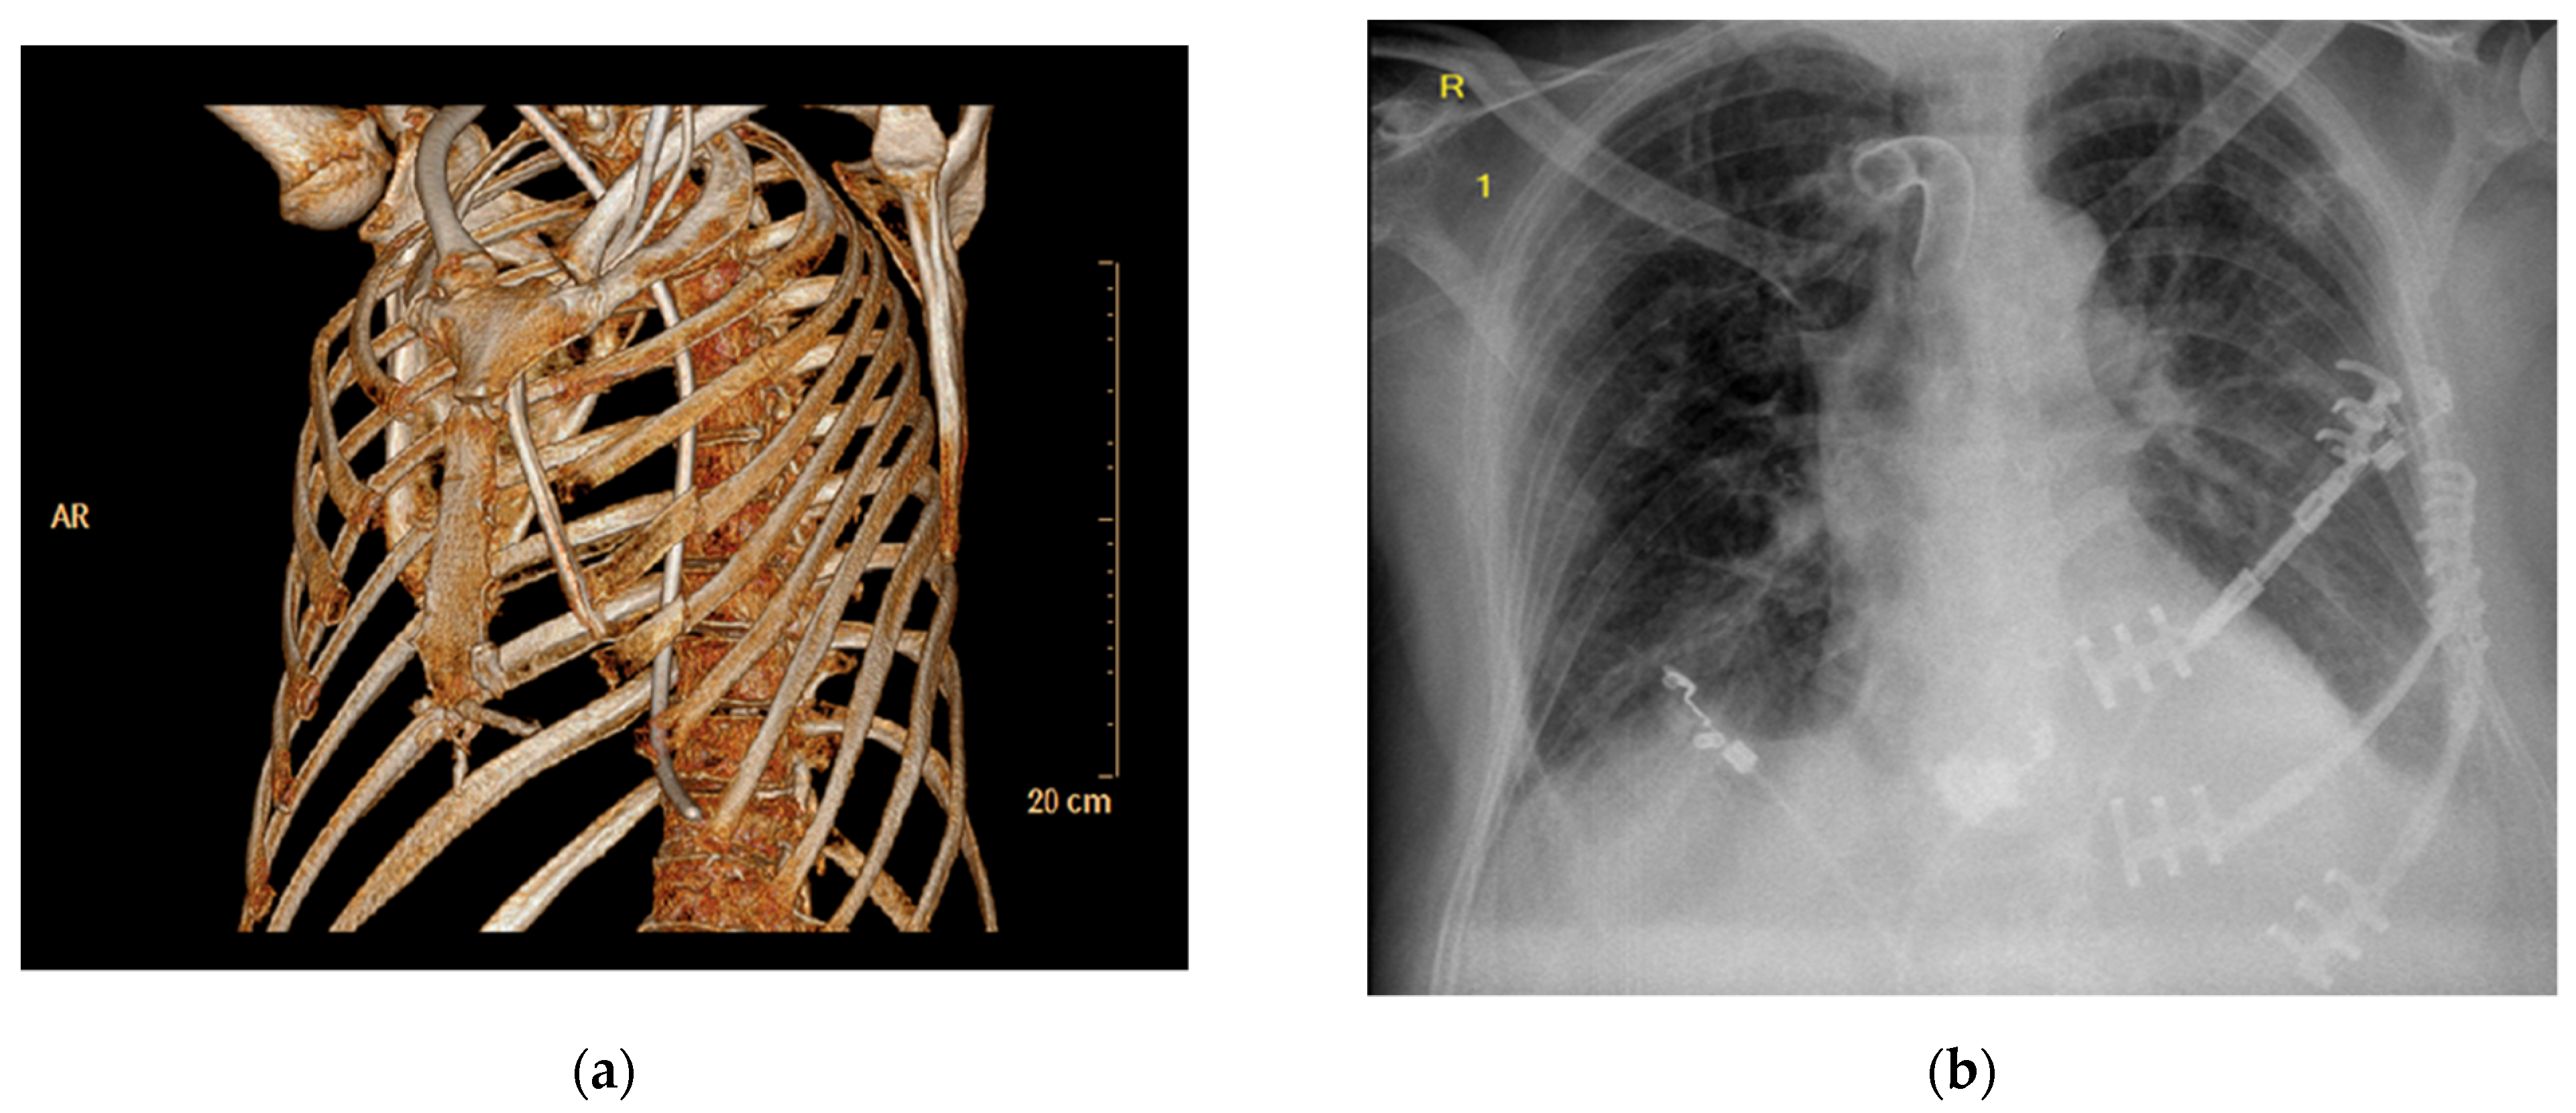

| Variable | Patient 1 | Patient 2 | Patient 3 | Patient 4 |

|---|---|---|---|---|

| Age | 61 years | 53 years | 61 years | 66 years |

| Sex | male | male | male | male |

| BMI [kg/m2] | 24.7 | 24.7 | 29.2 | 22.5 |

| Reason for CPR | Pulmonary embolism | Myocardial infarction | Myocardial infarction | Hypoxia |

| Relevant comorbidities | Aspiration pneumonia | Aspiration pneumonia | Influenza pneumonia Acinetobacter pneumonia | Aspiration pneumonia Heart failure COPD |

| Duration of CPR | 65 min | 20 min | 15 min | 21 min |

| Length of ICU stay | 45 days | 27 days | 69 days | 18 days |

| Mechanical ventilation | 37 days | 18 days | 59 days | 16 days |

| Number of fractured ribs | 9 ribs | 8 ribs | 7 ribs | 14 ribs |

| Anterior flail segment | Yes | Yes | Yes | Yes |